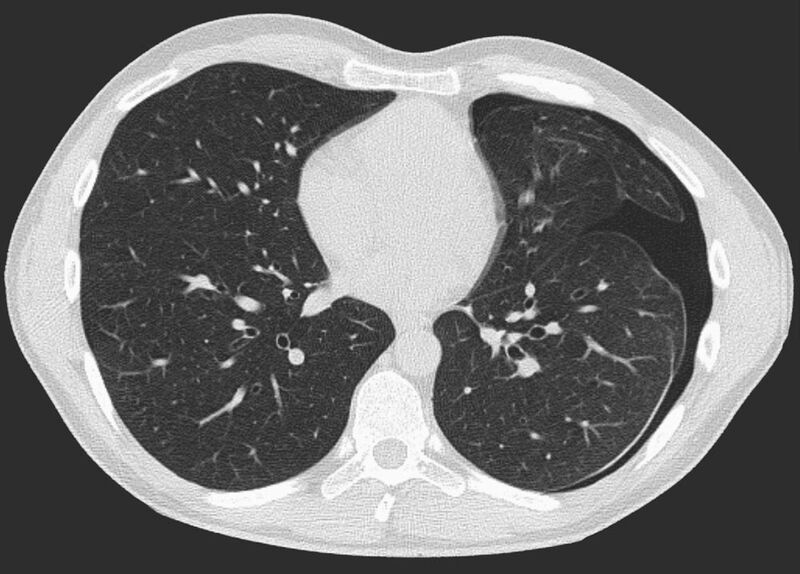

Thorax (Brustkorb)

• Entzündungen oder Tumore des Mediastinums und der Lunge

• Lungenembolie- Diagnostik

• hochauflösende Darstellung des Lungenparenchyms zur Abklärung chronischer interstitieller Erkrankungen wie z. B. Fibrosen, Emphysem, Bronchiektasen

Die Zeitspanne für die Untersuchung hängt von der Größe des Untersuchungsbereiches ab. Einzelne Untersuchungen dauern nur wenige Sekunden (die der Lunge z. Bsp. ca. 7 bis 12 Sekunden). Einschließlich Lagerung auf der Untersuchungsliege und der Planung der Untersuchungsbereiche ist eine solche Untersuchung insgesamt meist nach 5 bis 10 Minuten beendet.